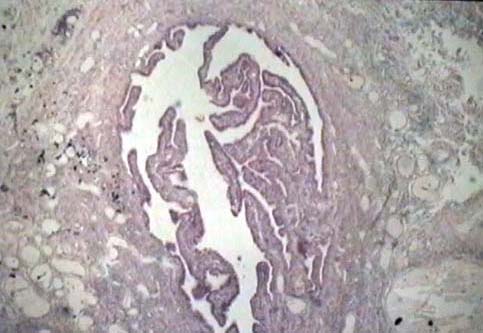

Niere und ableitende

Harnwege

Weiblicher Genitaltrakt